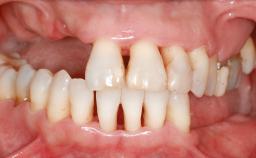

A 45-year-old woman with a completely edentulous maxilla was referred to evaluate the possibility of rehabilitation with an implant-supported prosthesis. This patient was healthy and a non-smoker. She had been wearing a maxillary complete denture opposing a natural mandibular dentition since her twenties. This situation had resulted in progressive resorption of the alveolar ridge, repeatedly creating a need for relining the denture. Twenty years later, despite multiple adaptations and the use of “glues” the denture was unstable and causing the patient psychological and functional discomfort.

| Soft Tissue Contour and Volume | Significantly deficient |